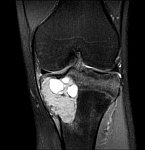

- Resection of benign and malignant tumors of the bone and soft tissue

- Reconstruction of bone defects by biological procedures (from spongiosaplasty to bone transfer)